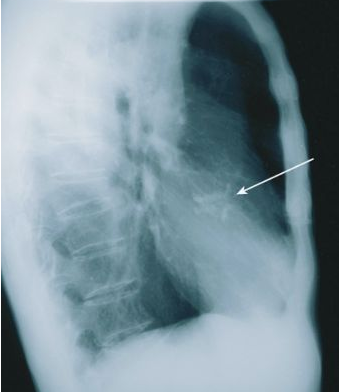

Investigations